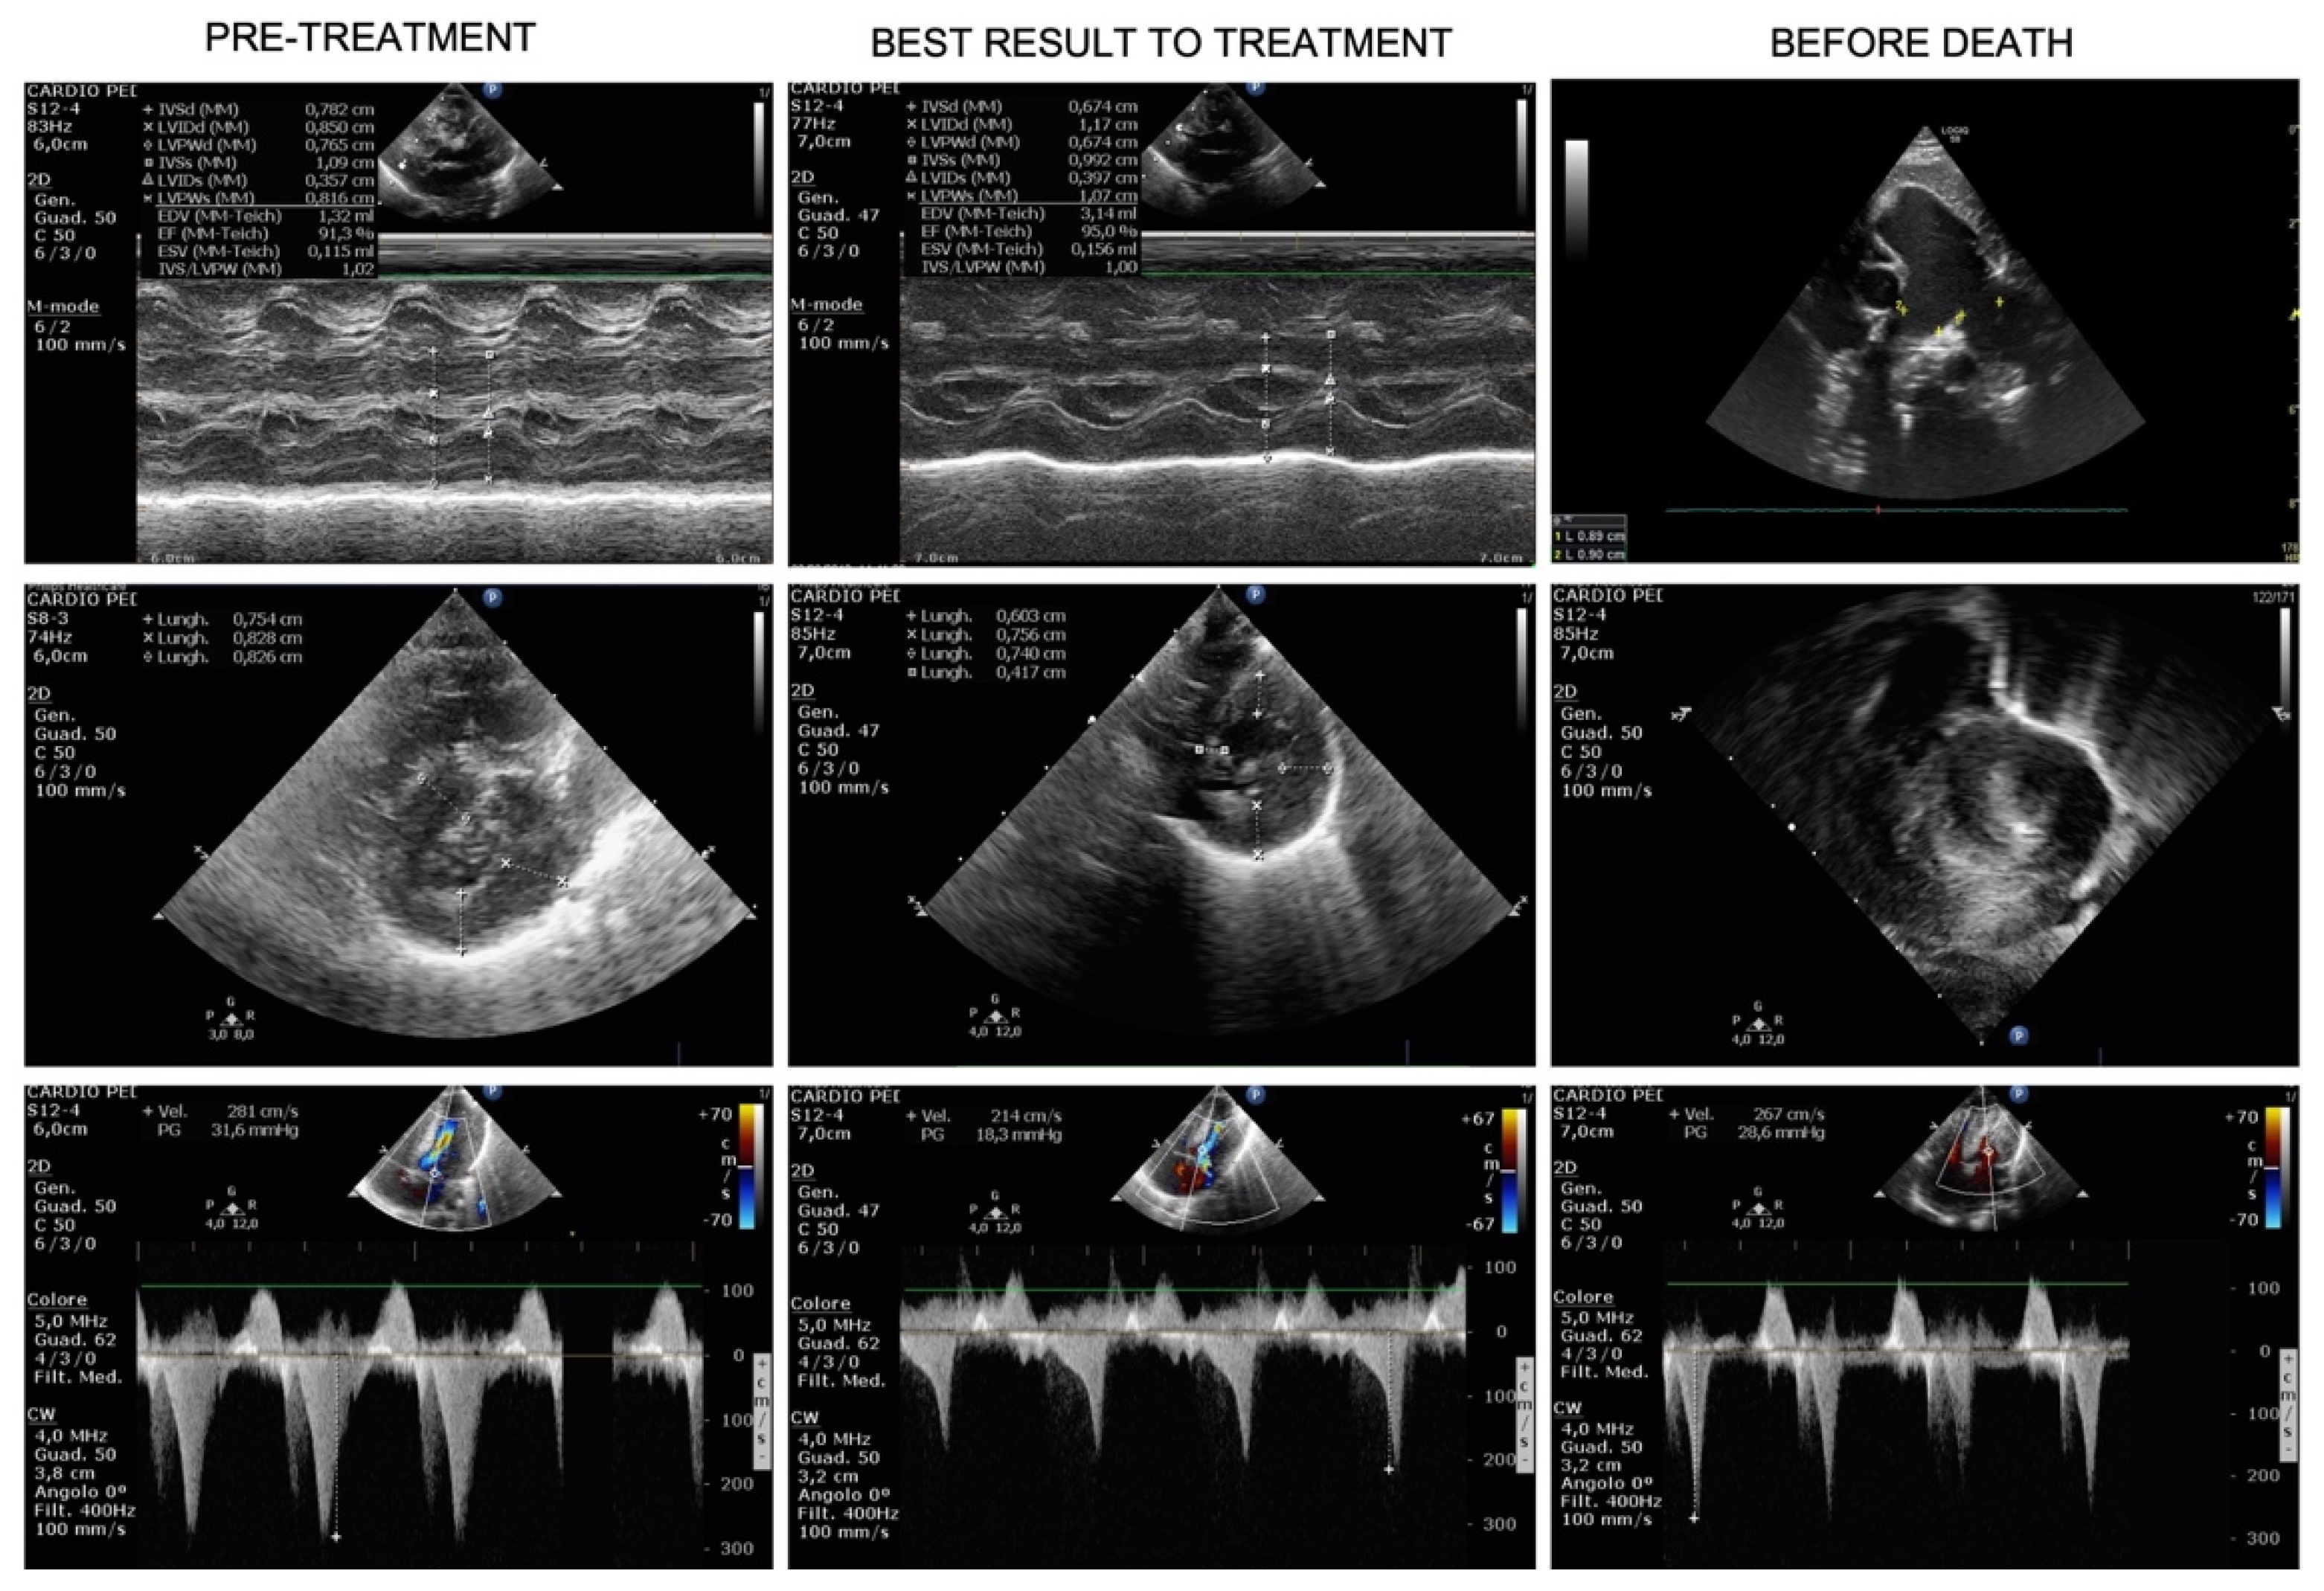

Figure 2.

Evolution over time of hypertrophic cardiomyopathy (HCM). Pre-treatment US (first column) shows severe HCM at M-mode Left Ventricle (Mm-LV, first row), short-axis LV (second row) and LV outflow track obstruction (CW-Doppler, third row), few days before treatment start. The best result under treatment is shown in the middle column: Mm-LV in first row, short-axis LV (second row) and LV outflow track obstruction (third row) demonstrated a consistent reduction of LV thickness and improvement of LV outflow track obstruction. The third column shows cardiac US three days before death: pulmonary artery dilatation is evident in the first row (2D), the rapid worsening of HCM, both in terms of LV thickness and obstruction are depicted in the last 2 rows (short-axis LV and CW-Doppler, respectively).

At day +46, a ventriculoperitoneal shunt was placed in order to manage the intraventricular hemorrhage and a red blood cell unit was transfused. After surgery, we observed rapid worsening of CHF (nt-pro-BNP increased from 2049 pg/mL to 47,000 pg/mL) as well as respiratory deterioration, requiring again mechanical ventilator support. Pulmonary artery dilation, stable until then, increased to 18 mm (+5.7 SDS) and death from untreatable CHF with hypoxic respiratory failure occurred on day +57. Figure 1 recapitulates the time course with septal thickness changes, left ventricular outflow (LVO) gradient and nt-pro-BNP changes across treatment. Figure 2 shows the ultrasound HCM evolution over time.

After treatment initiation there was a prompt improvement in clinical conditions (ROSS score from IV to III), allowing progressive and rapid withdrawal of inotropes in the next 4 days and weaning from mechanical ventilation a week later. Consistent with HCM stabilization, nt-pro-BNP decreased from 30,805 to 2355 pg/mL, and the patient was placed in non-invasive ventilator support and restricted fluid intake, with furosemide administration “as needed”. During the next month, treatment with Trametinib was continued without relevant side effects. ROSS score was II at 1 month. Liver enzymes, complete blood count, clotting tests, electrolytes, renal function were regularly monitored with no substantial modifications from baseline nor effects attributable to Trametinib administration. Echocardiography showed a tendency to HCM improvement with reduction of the septal thickness from treatment start to day +23. We also noted sudden dilation of the pulmonary artery dilation (14 mm, +3.5 SDS) at day 23. Despite of this finding, clinical conditions were stable in the following days and non-invasive ventilatory support was progressively reduced in terms of oxygen flow and fraction.